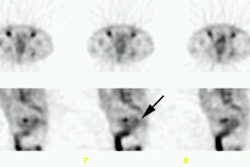

patients treated previously at the same institution but without CEA imaging. RESULTS: A

total of 219 CEA imaging studies were performed without any significant adverse effects or

immune responses, and resulted in lesion sensitivity, specificity, accuracy, and positive

and negative predictive values of 94.1%, 97.5%, 97.3%, 76.2%, and 99.5%, respectively. Of

the 40 patients, 16 developed 22 surgically confirmed local or distant recurrences, and

CEA imaging correctly disclosed 82% of these lesions pre-operatively. All of the patients

found to have recurrences had at least one tumor site by CEA imaging; only 6 of 16 had

elevated blood CEA titers. On a patient-basis, there was a sensitivity of 100%, a

specificity of 79.2%, an accuracy of 87.5%, and positive and negative predictive values of